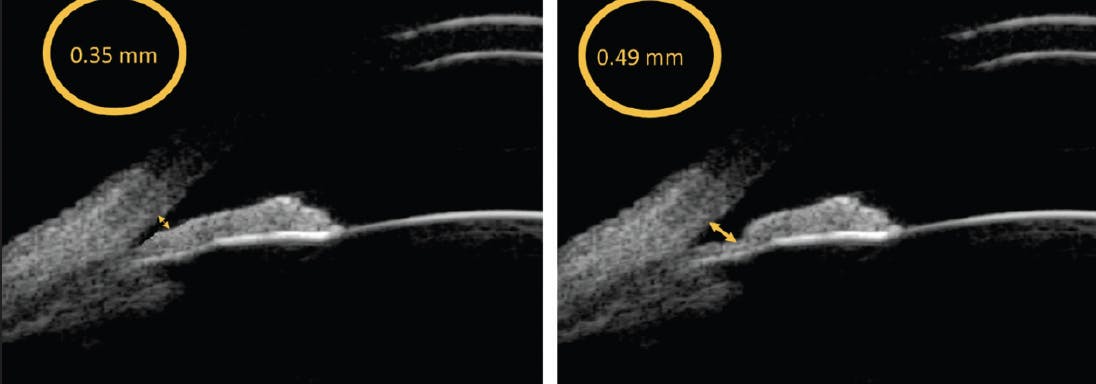

Any narrow angle is at risk for Plateau Iris. If the condition is associated with pupillary block, an eventual iridotomy is justified. If it presents alone, however, an iridotomy is ineffective; the treatment of choice in this situation is argon laser iridoplasty, and sometimes even lens extraction (Figure 3).16

Figure 3. Iridoplasty widens the angle in the periphery, allowing a greater filtration area of the trabeculum, even a small difference in distance between the trabeculum, and the iris is hydrodynamically important for this purpose; this is seen on UBM with the ABSolu device.